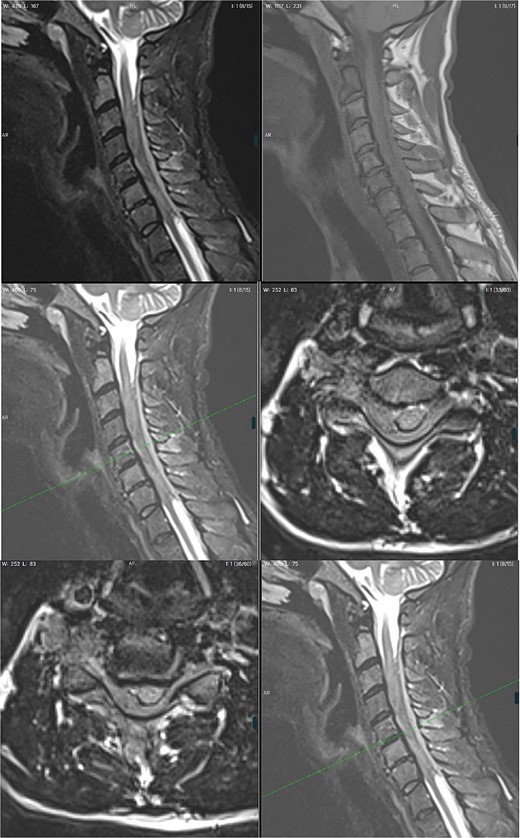

A 42-year-old man was admitted to the emergency department (ED) with progressing tetraplegia. A week earlier the patient had a session of spinal manipulation therapy (SMT), which he underwent due to his previous fall on a ship a few weeks before. During SMT, he heard a loud crack in his neck. The following day he woke up with numbness and weakness in his lower extremities, symptoms slowly progressed and after a week he was affected by tetraparesis and decided to seek help at the ED. The patient was fully conscious with a GCS score of 15. Further neurological examination revealed proximal and distal weakness of 3/5 in the Medical Reaserch Council (MRC) scale in both upper extremities. Greatest severity was noted in hand grip bilaterally, impaired touch sensation in ulnar nerve distribution bilaterally. In the lower limbs, weakness of hip flexors and extensors was graded 3/5 MRC, foot dorsiflexion and plantar flexion of 2/5 MRC. Impaired sense of touch and pain bilaterally from the level of the mid-thighs distally, pain and temperature sensation in the limbs was preserved. Pain and temperature sensation in the lower limbs was preserved. Deep tendon reflexes of the lower extremities were vivid and symmetrical. Moreover, the patient also presented with a bilateral positive Babinski sign. Ataxia could not be assessed due to paresis. Non-contrast Magnetic Resonance Imaging (MRI) visualized a lesion located at C3–C7 causing vertebral cord compression with abolition of the subarachnoid space and edema of soft tissues surrounding spinous processes. Increased signal of the C2 and C6 vertebral bodies in T2-weighted images suggested post-traumatic changes. Features of massive edema of the spinal cord over a section of ⁓10 cm (from the level of the lower part of the C2 body to the upper part of the T1 body), with the elimination of the perimedullary fluid space in this section—features of intracanal tightness were also observed. In the C3–C7 section, an extensive right-sided epidural hematoma was suspected (Fig. 1.). The radiological diagnosis was extensive spinal cord compression by spinal epidural hematoma in the cervical region. The patient was admitted to the Neurosurgery Department and qualified for emergent surgery. A C3–C7 laminectomy was performed. After removing the ligamentum flavum, no sign of hematoma could be noticed. Instead a tumorous mass was found overlaying the thecal sac. Due to dura infiltration a subtotal resection was performed in order to decompress the spinal cord. Samples were sent for post-op histopathological examination. The following day, the patient was extubated as his condition improved. The day after surgery, with the assistance of a physiotherapist, the patient was placed in an upright position and walked with the help of a walking frame. Over the recovery period of 8 days, gradual amelioration of previous neurological symptoms occurred with his overall state being stable. Rehabilitation counseling was ordered in which tetraplegia, flaccid paresis in the upper limbs, more severe distally, and spastic paresis in the lower limbs were still described. No sensory disorders were detected. Generalized muscle atrophy was noticed. After pathomorphological evaluation the diagnosis of diffuse large B-cell lymphoma (DLBCL) was made. The patient was discharged home to wait for further oncological treatment. On the 17th day after discharge, the patient returned to the ED due to progression of limb paresis. He was then referred to the Oncology and Radiotherapy Department, where radical radiotherapy was administered. In the next few days the patient presented with fever and increased inflammatory parameters were noticed. Chest X-ray revealed bilateral pneumonia with fluid in the left pleural cavity resulting in pleural drainage. Due to the lack of improvement in the patient's condition after 40 days of hospitalization, bronchofiberoscopy was performed. During the procedure, bleeding from the respiratory tract occurred further complicated by cardiac arrest in the asystole mechanism. Successful cardiopulmonary resuscitation was performed. The patient was transferred to the Anaesthesiology and Intensive Care Department. During the next 2 days, the patient remained sedated and intubated, with no apparent improvement. With symptoms of multiple organ dysfunction, the patient suffered a second cardiac arrest. Due to exhaustion of further treatment options, resuscitation activities were not performed and the patient died.

Of all the lymphomas 0.1%–6.5% are observed in epidural location. Primary spinal epidural lymphoma (PSEL) is a subset of lymphomas, with which there are no other recognizable sites of disease at the time of diagnosis [3]. With PSEL, ˃80% patients were older than 40 years, the thoracic spine affected 75%, with 10% lesions in the cervical region [3]. In the earliest papers, overall survival was 6 months, with a median survival of 42 months in newer studies [3]. The misdiagnosis of epidural hematoma could have been caused by several reasons: previous trauma, which resulted in the patient underwent SMT and neurological deficits that appeared the next day, radiological features of the post-traumatic changes and lack of oncological history. Most reports assert that spinal epidural hemorrhage is caused by SMT [4]. Strong pressure on the cervical spine during SMT, immediate progression of neurological deficits and swelling of the soft tissues around the cervical spine, mostly pronounced in the area of the spinous processes, suggested post-traumatic changes. This was additionally indicated by a neck crack sound, which the patient mentioned at admission to the ED. Secondly, due to a traumatic history and continuous deterioration an urgent MRI examination of the cervical spine was performed without intravenous contrast agent. In a non-contrast MRI, the signal characteristics of an epidural lymphoma are very similar to those observed in a hyperacute or acute hematoma on both T1- and T2 turbo spin echo-sequences, before the spontaneously bright T1-signal of methaemoglobin emerges in the subacute stage [2]. Due to the patient's lack of cancer history and clinical indications from the collected interview, an MRI with contrast was not performed. The radiologist suggested post-traumatic changes with the diagnosis of epidural hematoma. This led to an emergent surgical decompression procedure. According to Lorenz Vangeel et al. Homogeneous contrast enhancement as expected in lymphoma would have made this a more straightforward diagnosis, in particular in the clinical setting of systemic lymphoma [2]. A suggestive medical history, with acute symptomatology and a radiological diagnosis led to surgical treatment. With PSEL a laminectomy was not associated with clinical improvement rates of previously known lymphoma patients with spinal cord compression nor laminectomy combined with chemotherapy and radiotherapy did prolong survival. Yet in cases with unknown diagnosis at the time of presentation, surgical decompression with tumor removal or decompressive laminectomy is indicated with the benefit of obtaining samples with the correct histological diagnosis [3].